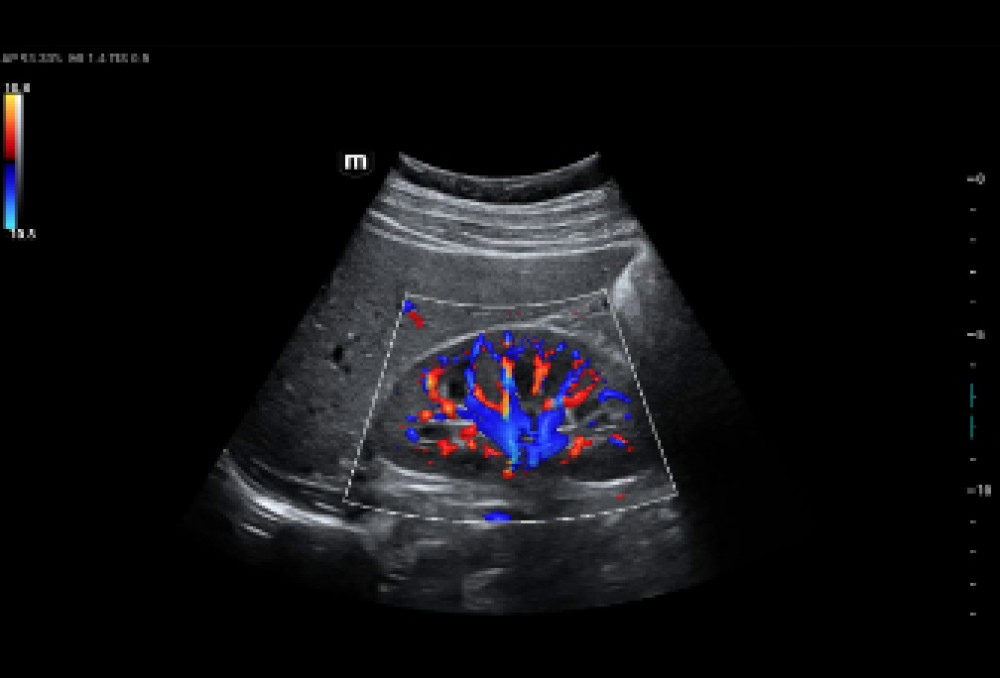

Ultra Micro Angiography (UMA): Mikro-sirkulyasiyanın detallı vizuallaşdırılması